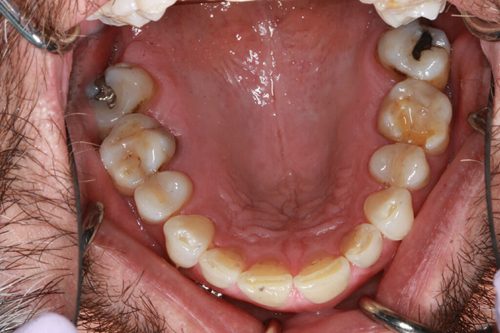

A male patient underwent tooth-colored fillings and dental crowns by Dr. Jeffrey A. Weller in Chicago, IL, in May 2018. Following the procedures, the patient reported a positive experience, expressing satisfaction with the results. The clinical team’s meticulous work and Dr. Weller’s expertise were highlighted, contributing to a successful outcome. The patient left the clinic with improved dental health and a confident smile, grateful for the professional care received.

Before